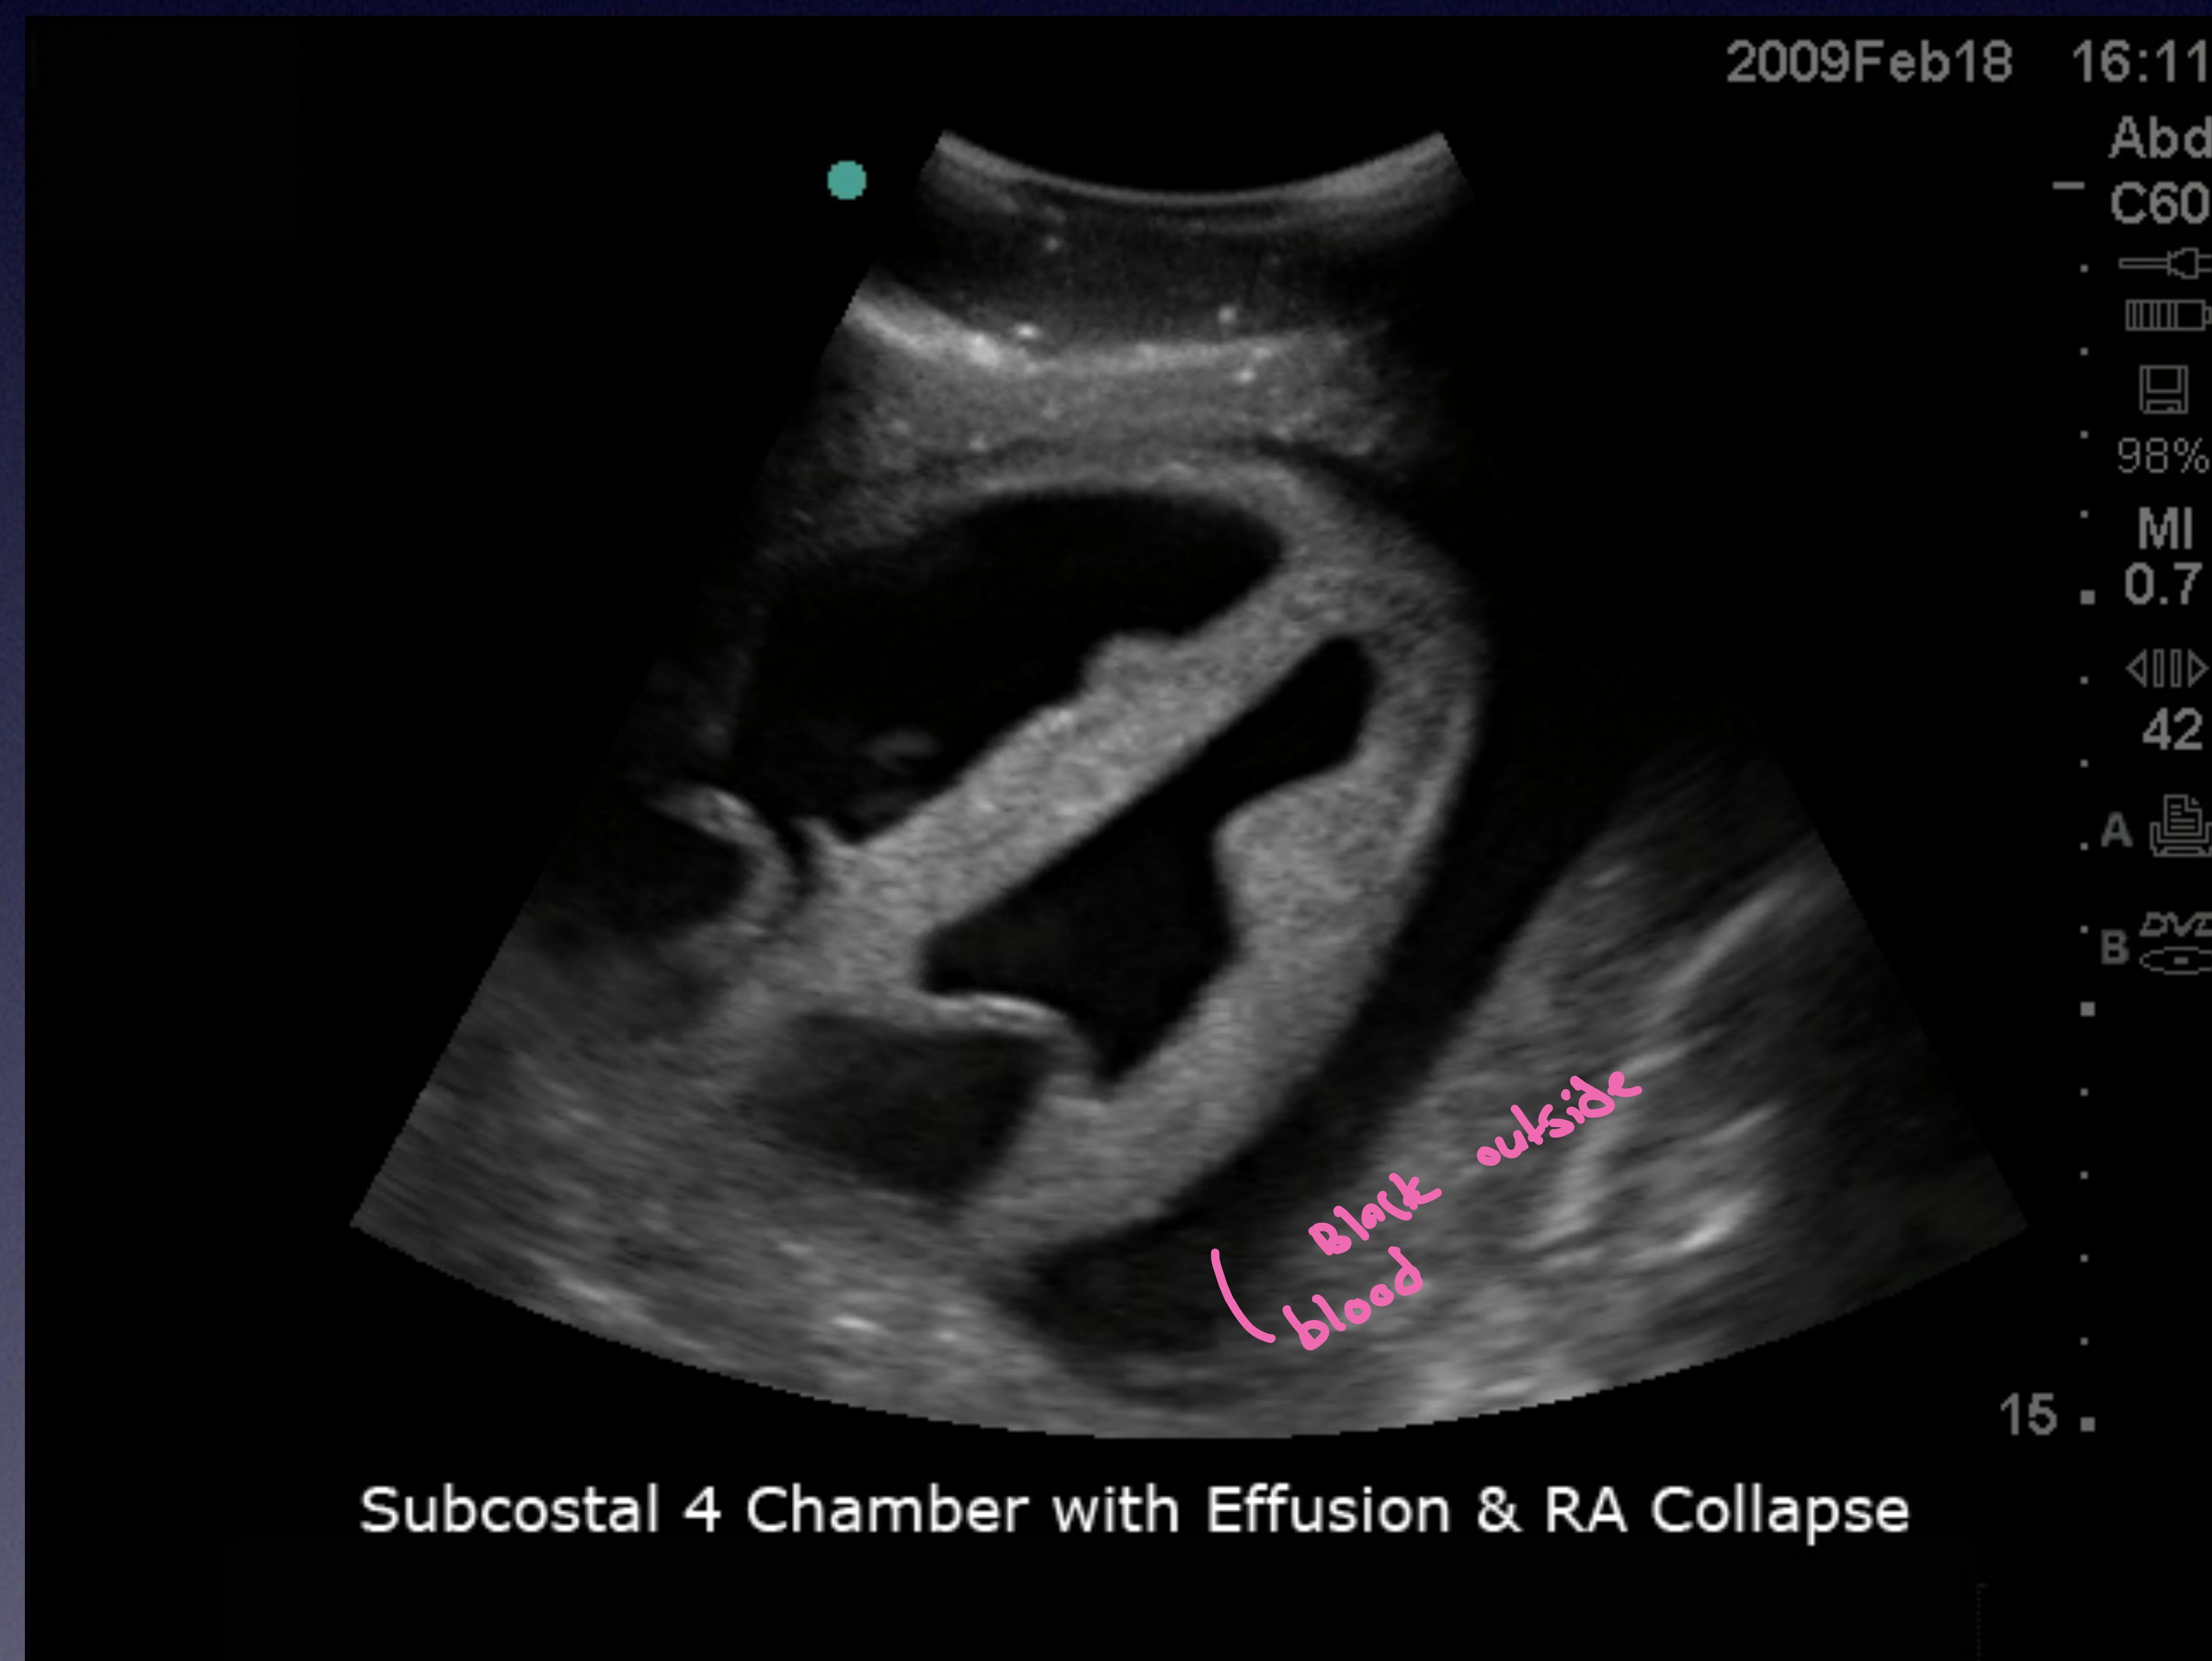

Pericardial Scan

Pericardial space showing fluid accumulation (effusion).

Subcostal 4 Chamber view with Effusion & RA Collapse.